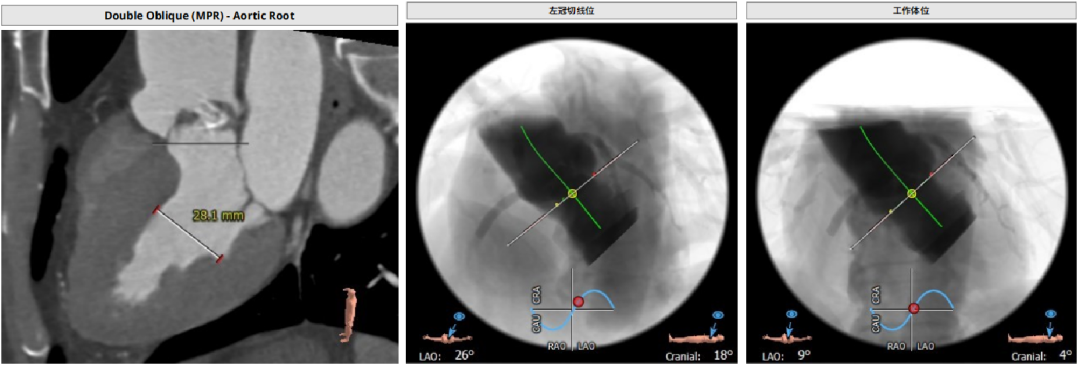

CT分析

Anulus 25.7、LVOT 23.7;STJ高度可,窦部空间足够;初步预估29/32瓣膜。

升主未见增宽,角度尚可,轻度钙化。

左右冠高度不低,球扩体位:LAO 26、CRA 18;释放体位:LAO 9、CRA 4;心室腔略小。

入路直径足够,分叉点足够高。右股作为主入路。